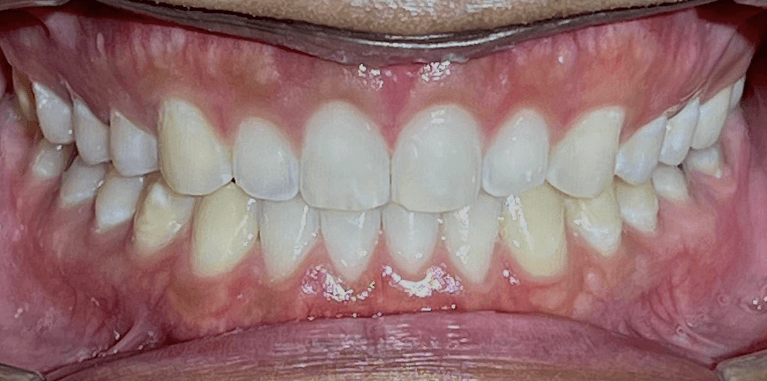

Invisalign Orthodontic treatment completed in 8 months to straighten teeth and improve esthetics.